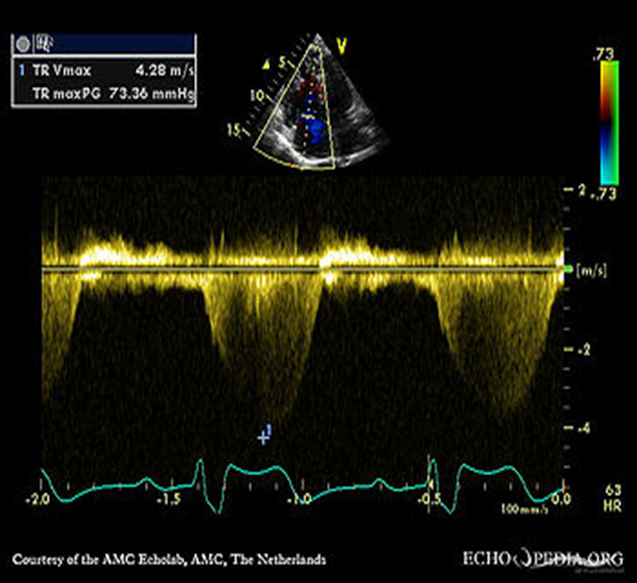

Right Ventricular Systolic Pressure (RVSP) is used to

RVSP is used to estimate right side pressures in the vessels leading to the lungs. This is used to determine pulmonary hypertension.

TR Vmax + RAP= RVSP

How to obtain the rsvp/spap

1. Place the CW cursor through the TR color jet

2. Measure the tricuspid regurgitant waveform to achieve the tr velocity

3. The machine will use the TR Vmax velocity and turn it into a pressure gradient. This is done by using the Bernoulli equation

RVSP / Systolic pulmonary artery pressure (SPAP) determined by the TR

TR Max PG + RAP = RVSP/SPAP